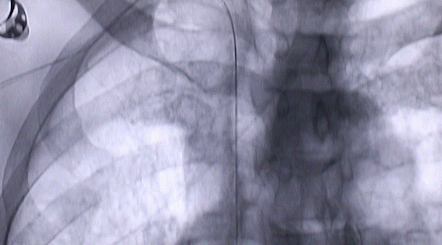

1月12日,西安國(guó)際醫(yī)學(xué)中心醫(yī)院心臟外科郭穎強(qiáng)主任團(tuán)隊(duì)成功為一名腹主動(dòng)脈閉塞、右側(cè)腎動(dòng)脈閉塞、左側(cè)腎動(dòng)脈重度狹窄、腹壁淺表動(dòng)脈側(cè)支循環(huán)形成、高血壓病3級(jí)(極高危組)合并閉塞性周圍動(dòng)脈粥樣硬化、急性腎功能不全的老年患者實(shí)施腎動(dòng)脈球囊擴(kuò)張 腎動(dòng)脈支架植入術(shù) 動(dòng)脈血栓抽吸術(shù) 髂動(dòng)脈開(kāi)通術(shù),治好了困擾患者多年的頑固性高血壓?;颊吣壳翱祻?fù)良好,將于近日出院。

按照術(shù)前制定的方案,郭穎強(qiáng)主任和楊金保博士首先嘗試開(kāi)通閉塞的右腎動(dòng)脈,但由于血栓機(jī)化、鈣化嚴(yán)重,右腎動(dòng)脈難以開(kāi)通。遂謹(jǐn)慎擴(kuò)張狹窄的左腎動(dòng)脈,并成功植入一枚支架。之后經(jīng)過(guò)反復(fù)旋磨、抽吸,順利開(kāi)通髂動(dòng)脈,但腹主動(dòng)脈閉塞段仍難以擴(kuò)通。此時(shí),患者居高不下的血壓很快恢復(fù)到正常水平。